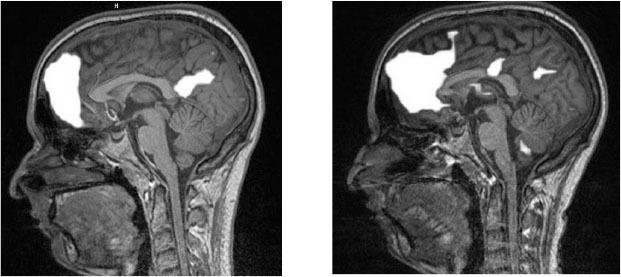

– Почему бы не сделать фМРТ его мозга до и после лечения?

Функциональная магнитно-резонансная томография, или фМРТ, – это томография, которая показывает активность головного мозга[4]. Я подумал, что было бы интересно посмотреть, как изменится мозг Кейси, когда он избавится от боли. Тогда я еще не знал, что это случайное предложение приведет к одному из самых революционных исследований в истории боли.

…томография, которая показывает активность головного мозга. – Функциональная магнитно-резонансная томография (фМРТ) регистрирует изменения кровотока в мозге. Когда какая-то часть мозга напряженно работает, к этой области приливает больше крови, и фМРТ показывает, какие участки мозга активны. Мы надеялись, что увидим другую картину активности в мозге Кейси, когда он избавится от хронической боли.

По просьбе продюсеров передачи «Врачи» мы сделали фМРТ мозга Кейси до начала лечения и по его окончании[17]. В медицинской литературе полно фМРТ-снимков людей, испытывающих боль разной интенсивности, однако никому в голову не пришло изучить, как выглядит мозг после излечения от хронической боли. Будут ли в мозге Кейси заметные изменения?

Мозговая активность Кейси до начала лечения